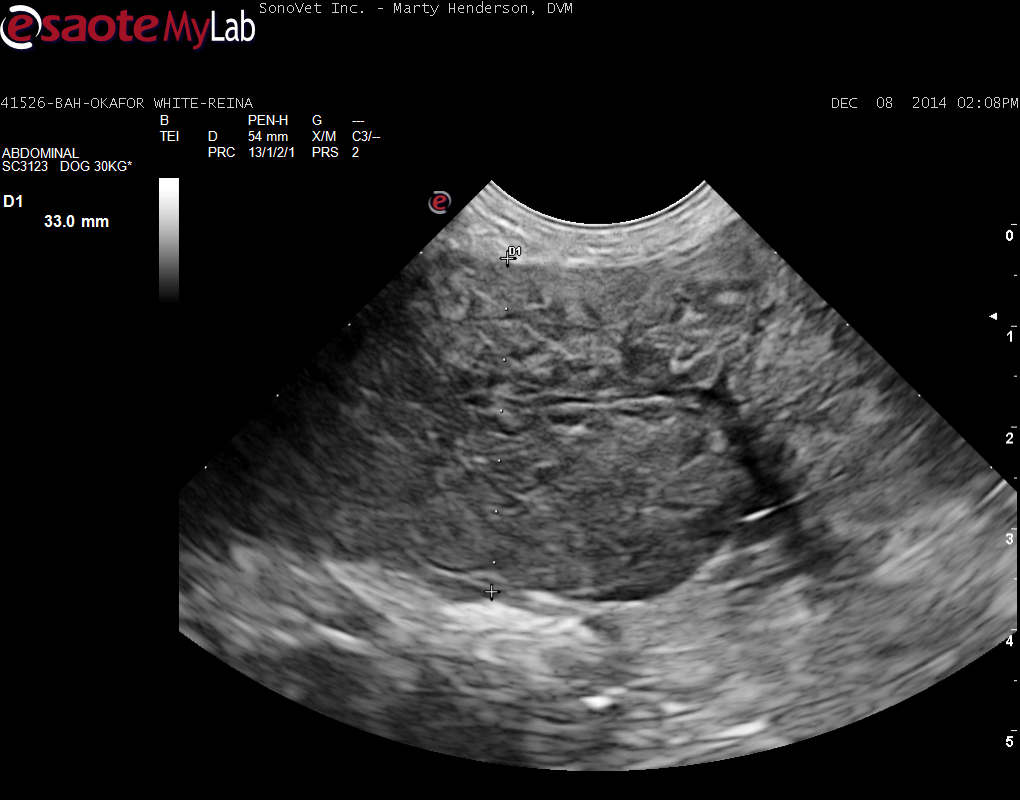

A 6-year-old female Labrador was presented for evaluation of loose stools and weight loss. Abnormalities on serum biochemistry were elevated liver enzyme activity and hypoalbuminemia. On survey thoracic radiographs, a mild interstitial pulmonary pattern was evident.